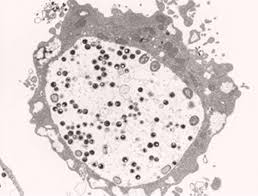

(3) 사람면역결핍바이러스(HIV)

① 개요

AIDS를 유발하는 바이러스로, 면역력을 저하시키고 다양한 합병증을 초래합니다.

② 증상

- 초기: 감기와 유사한 증상

- 무증상기: 수년간 별다른 증상 없음

- 진행기: 반복 감염, 체중 감소, 피로

- 치료하지 않으면 생명을 위협하는 후천성면역결핍증(AIDS)으로 진행